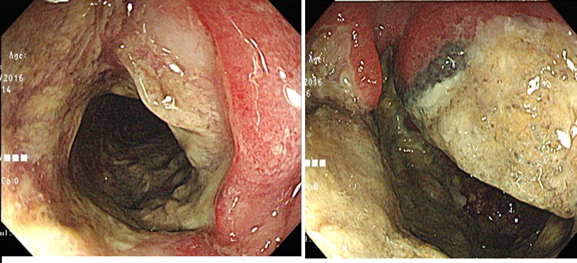

潰瘍性大腸炎と誤診され急激に悪化した大腸のDLBCLリンパ腫

最初の内視鏡と生検で「潰瘍性大腸炎」と診断されたが治療が全く効果が無く、2度目の内視鏡の生検でリンパ腫と診断。初発であり「長期経過の潰瘍性大腸炎に悪性リンパ腫が発生した」ものではなく「腸炎様のリンパ腫」であると結論している。過去に20件ほどの“colitis-like”

diffuse-type colorectal lymphomaの報告があるとのこと。